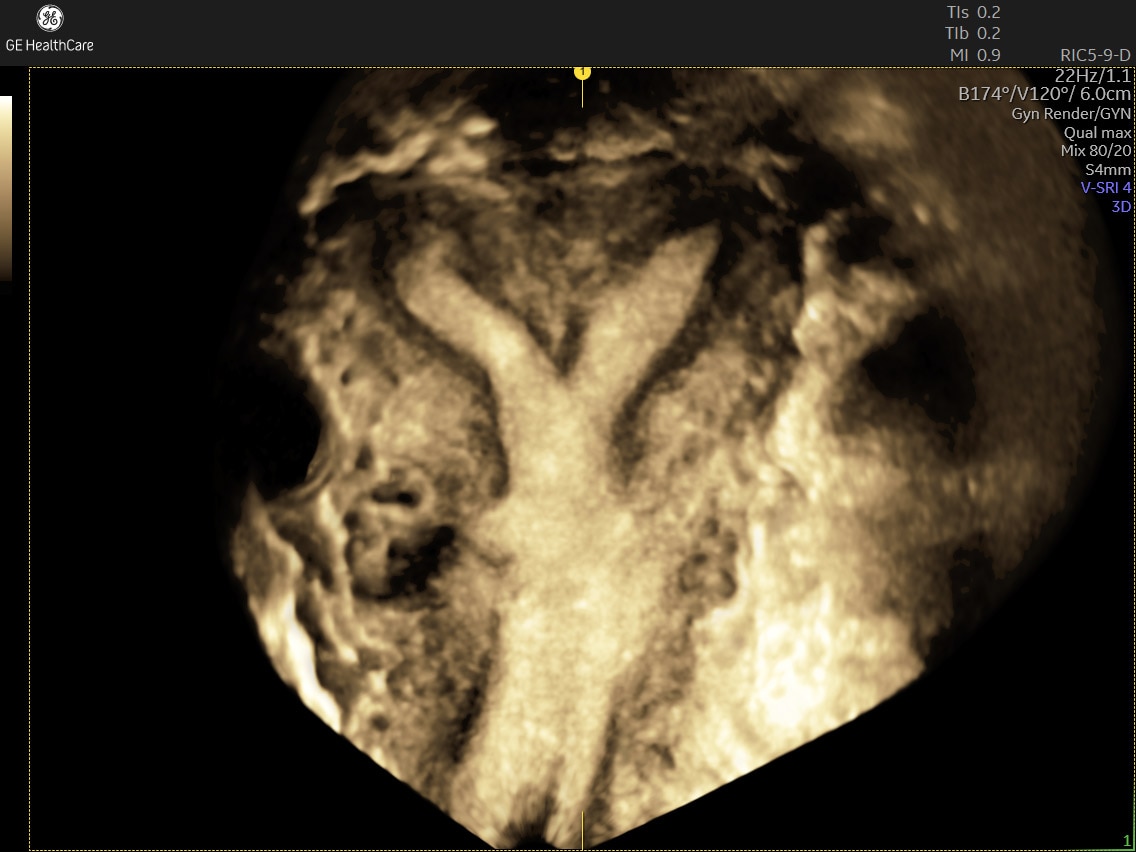

Amplify imaging performance and simplify scanning with our most advanced architecture

Refine Clinical Insights

Extraordinary clarity and definition so you can focus on early detection and intervention.

Faster.Sharper. Clearer.

Faster.Sharper. Clearer.